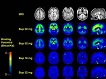

স্বপ্ন বিজ্ঞানঃ অবাস্তবতার কার্যকারণ [পর্ব-২]

pet-scan